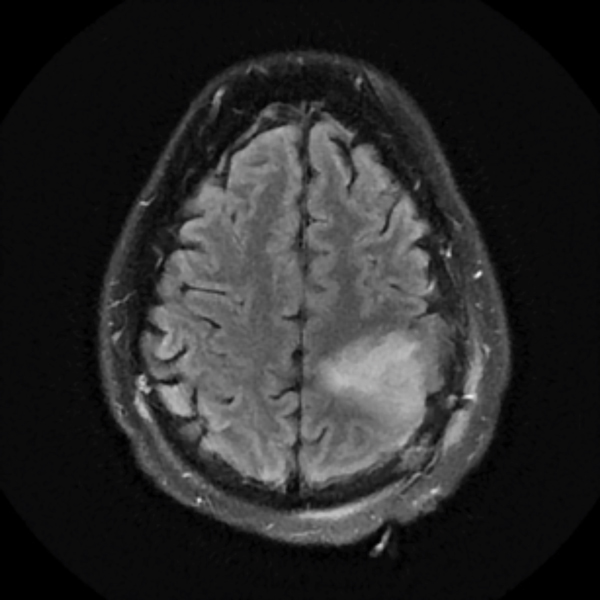

July 2019

A brain MRI showed an increased T2 signal in the left frontoparietal area. His tumor was non-enhancing. He underwent a partial resection of the tumor performed by NSPC neurosurgeon Ramin Rak, M.D., with intraoperative monitoring revealing eloquent motor cortex involvement anteriorly. The pathological diagnosis was WHO grade 2 oligodendroglioma.